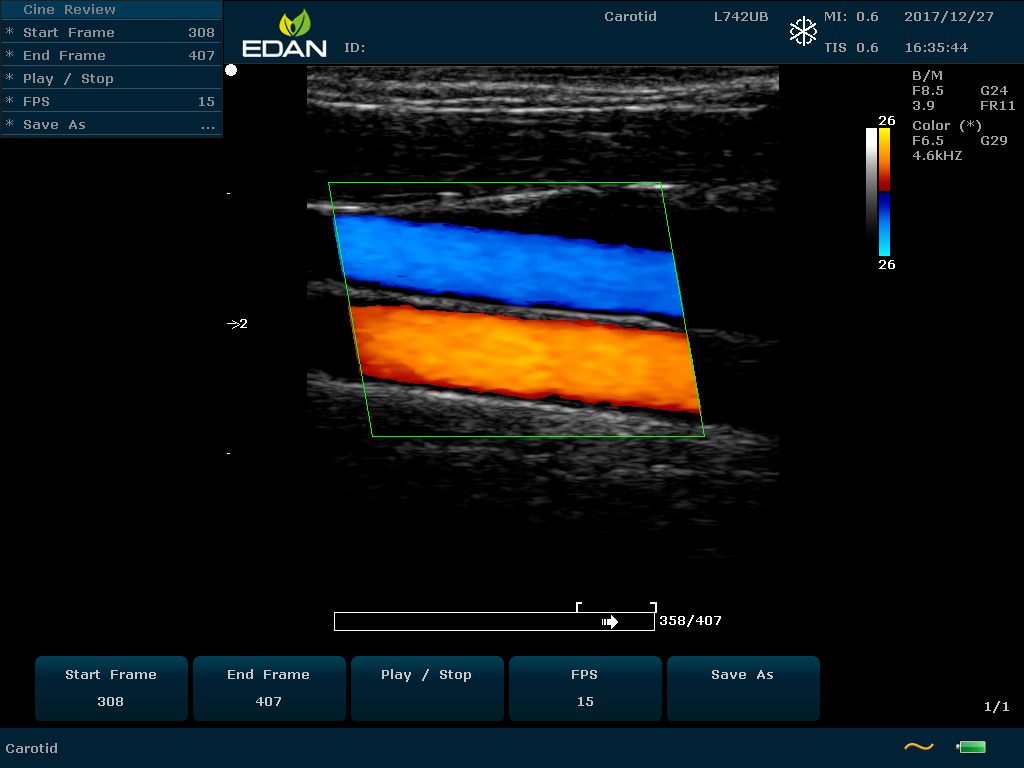

Особенность U60 Edan — расширенное применение. Ультразвуковой аппарат рекомендован для абдоминальных исследований, гинекологии и акушерства, кардиологии, педиатрии, урологии, изучения малых органов, сосудов. Для U60 Edan используются конвексные, линейные, фазированные и внутриполостные датчики.

Передовые технологии позволяют повысить качество визуализации в несколько раз. УЗИ-аппарат U60 Edan отличается возможностью быстрой настройки визуализации. Специальные функции позволяют моментально отображать данные за счет быстрой оптимизации параметров. Режимы визуализации: B-mode, M-mode, Color Doppler, Power Doppler Imaging, Pulsed Wave Doppler, Continuous Doppler.

• Цветовое Допплеровское картирование